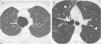

La patología de las vías respiratorias de medio calibre (bronquios segmentarios y subsegmentarios) es común y se presenta con síntomas respiratorios poco específicos, como tos, infecciones de repetición y en ocasiones hemoptisis. La dilatación permanente del árbol bronquial se conoce como «bronquiectasia» y representa un reto diagnóstico. El análisis de la distribución regional de las bronquiectasias en los diferentes lóbulos pulmonares es la guía diagnóstica más útil. El objetivo de este trabajo es describir los hallazgos de imagen de las bronquiectasias y sus diferentes tipos, revisar las situaciones más comunes y proponer un algoritmo diagnóstico basado en su distribución anatómica. Las bronquiectasias son un hallazgo frecuente, resultado de un amplio espectro de enfermedades. Los estudios de imagen desempeñan un papel esencial en su detección, clasificación y orientación diagnóstica hacia la patología subyacente

Diseases that involve the medium caliber airways (segmental and subsegmental bronchi) are common and present clinically with nonspecific respiratory symptoms such as cough, recurrent respiratory infections and occasionally, hemoptysis. The abnormal and irreversible dilation of bronchi is known as “bronchiectasis”. The diagnosis can be challenging and the analysis of the regional distribution of the bronchiectasis is the most useful diagnostic guide. The objective of this manuscript is to describe the main imaging findings of bronchiectasis and their classification, review the diseases that most commonly present with this abnormality, and provide an approach to the diagnosis based on their imaging appearance and anatomic distribution. Bronchiectasis is a frequent finding that may result from a broad range of disorders. Imaging plays a paramount role in diagnosis, both in the detection and classification, and in the diagnosis of the underlying pathology.